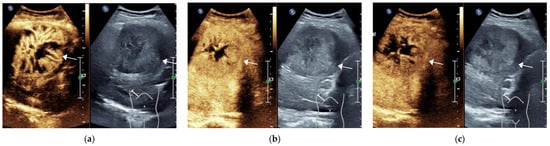

| Group | Num. | Enhancement Pattern in AP | Degree of Wash-Out | Time to Wash Out/s | ||||||

| Non-Rim APHE | Rim APHE | Non APHE | Mild | Marked | Non | <60 | ≥60 | Non-Wash Out | ||

| HCC | 61 | 58 (95.1%) | 2 (3.3%) | 1 (1.6%) | 54 (88.5%) | 3 (4.9%) | 4 (6.6%) | 11 (18.0%) | 46 (75.4%) | 4 (6.3%) |

| OM | 38 | 14 (36.8%) | 22 (57.9%) | 2 (5.3%) | 13 (34.2%) | 25 (65.8%) | 0 (0%) | 32 (84.2%) | 6 (15.8%) | 0 (0%) |

| X2/t | - | 40.745 | 43.373 | 41.946 | ||||||

| p | - | <0.001 | <0.001 | <0.001 | ||||||